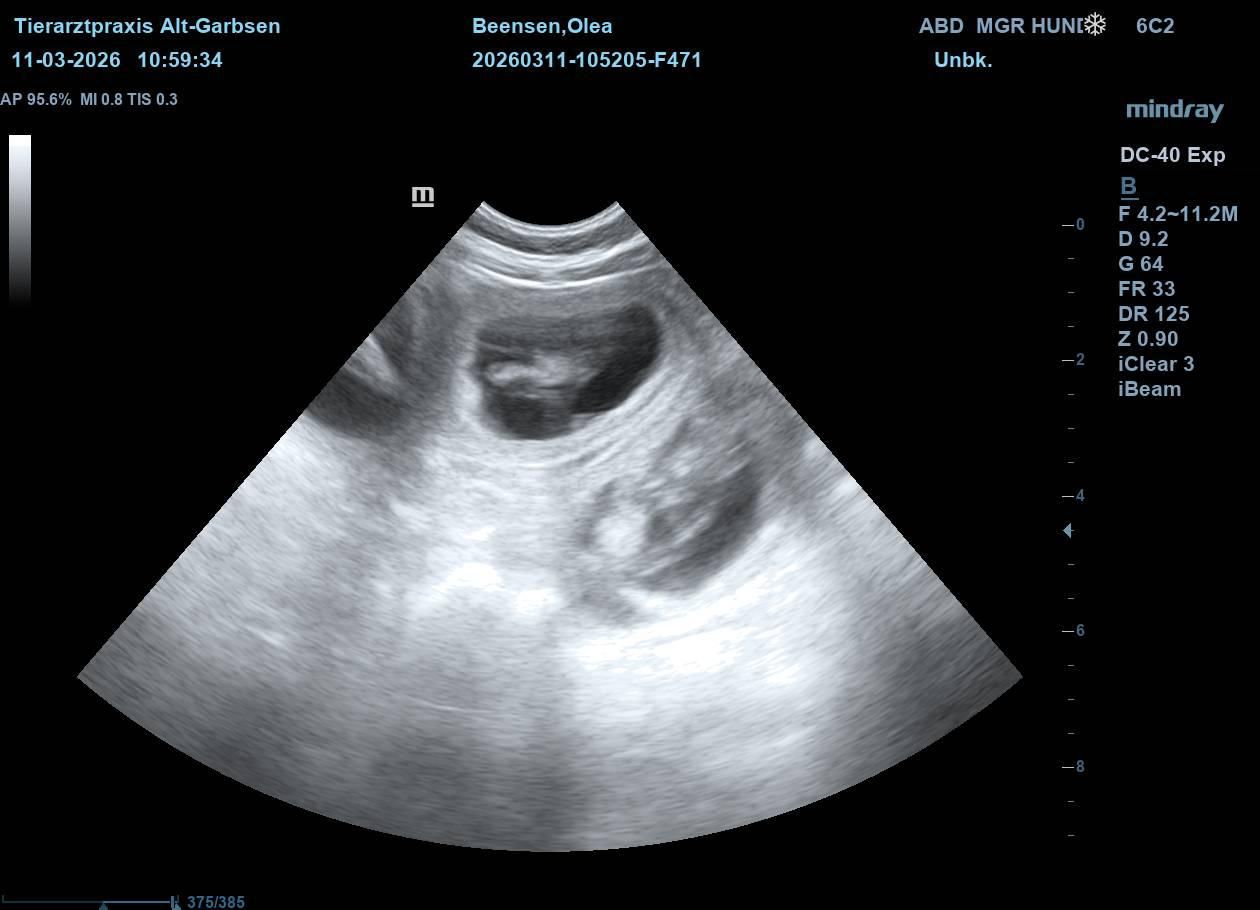

Update vom 11.03.2026:

Heute war ein ganz besonderer Tag. Olea war zum Ultraschall. Schon seit einigen Tagen hatten ihre Besitzer das Gefühl, dass sich etwas verändert hat. Sie war ruhiger und anhänglicher geworden - und ihr Bäuchlein schien sich leicht zu runden.

Beim Ultraschall war es dann eindeutig. Kleine, deutlich erkennbare Welpen. Auf dem Bildschirm waren mehrere winzige Herzschläge zu sehen. Freude, Aufregung und Ehrfurcht - alles zusammen stellte sich bei den Besitzern ein. Olea lag ganz entspannt - als wüsste sie, dass in dem Moment etwas ganz Wundervolles passiert. Jetzt beginnt die spannende Zeit der Vorbereitung. In den nächsten Wochen wird alles für die Ankunft der kleinen "vom Jademeer´chen" vorbereitet. Nicht mehr lange.....